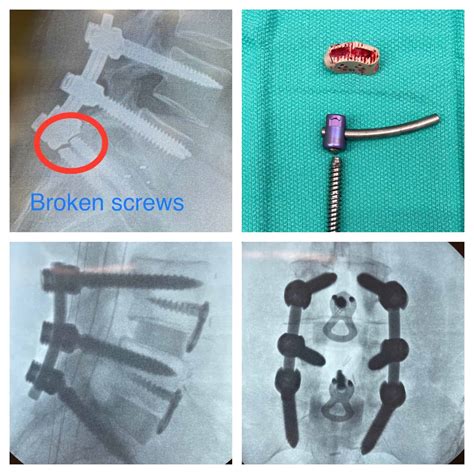

Sometimes, despite our best efforts, the initial surgery doesn’t completely solve the problem, or a new issue pops up later on. That’s when revision surgery comes into play. A revision surgery is a second procedure to address the issues that remain. It’s like a do-over, but with a different set of challenges and considerations. Let’s delve into what revision surgery entails and what you need to know. The reasons for revision surgery are varied. It could be due to continued pain, implant failure (in the case of joint replacements), infection, or even a lack of improvement after the initial surgery. Sometimes, the initial surgery might have been successful, but new problems develop over time. Whatever the reason, revision surgery aims to correct or improve the outcome of the first procedure.

So, what does this mean for you? Well, if you are told you need revision surgery, the first step is to learn as much as you can about it. Ask your doctor questions, gather information, and understand why the revision is being recommended. You should also consider getting a second opinion. Having a better idea will help you make an informed decision. Then, the pre-operative process is similar to the first surgery, with medical evaluations, imaging tests, and discussions with your healthcare team. The surgery itself might be more complex than the first one. It could involve removing old implants, repairing damaged tissues, or correcting previous errors. Post-operative care will also be similar, with a focus on pain management, wound care, and rehabilitation. Your recovery could take a longer time to get back on your feet. The goal of revision surgery is to improve your quality of life, reduce pain, and restore function. Revision surgery isn’t always the ideal situation, but it can be really important to get you back to feeling your best. It’s a journey, not just a one-time fix. If it becomes a part of your journey, approach it with an informed, positive mindset. Remember, it’s okay to feel overwhelmed. Surgery is always a lot, and revision surgery is no exception. With the right care and the support, you can get the best possible outcome. Also, seek support from your loved ones. Communicate with your healthcare team. Make sure to approach it with a level head, a positive attitude, and focus on the goal – which is improving your quality of life. Be kind to yourself, follow your doctor’s instructions, and be patient. You will find yourself back to your normal routine with this process.